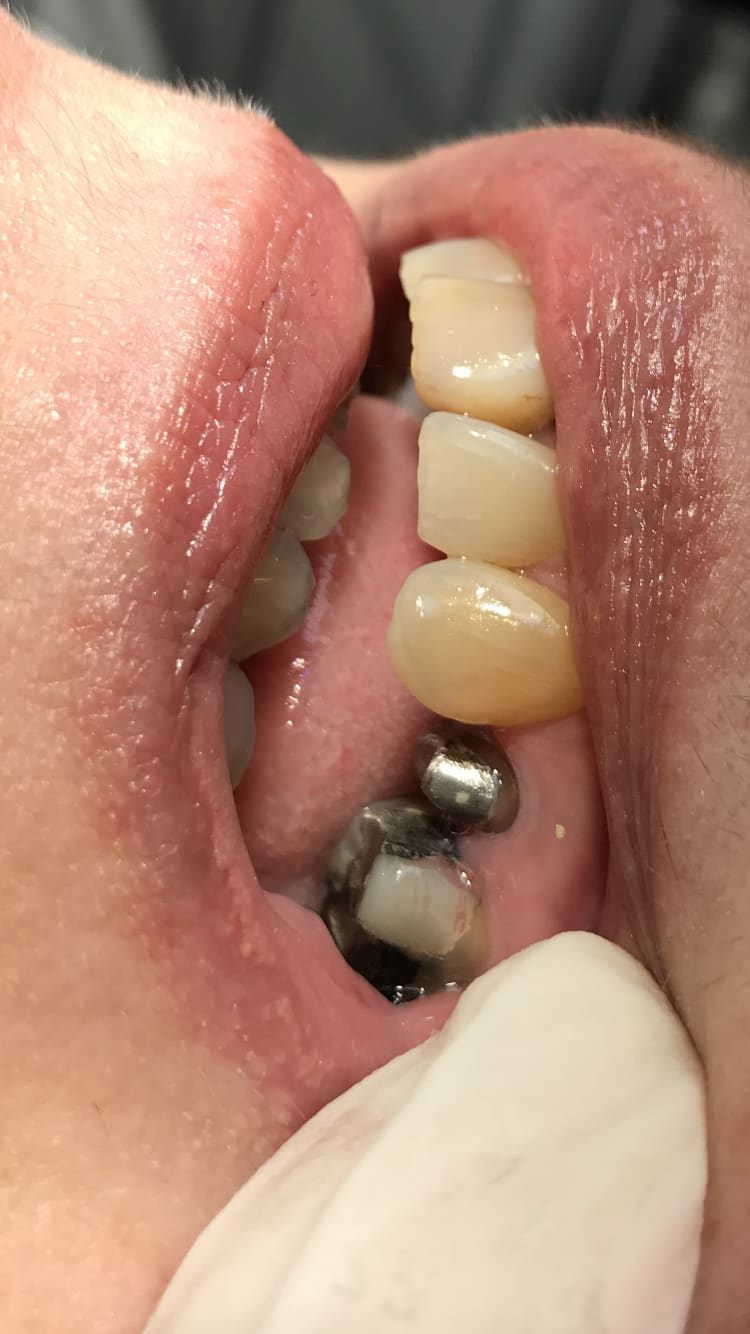

Regarde pépère avant la pose , j’ai pas fait gaffe je l’ai pas enfoncé à fond pour faire la photo. La 14 c’est du chinois avant que je la colle.

7e3fad7d 16a0 47d7 b578 45cde48756f3 sxy7dd - Eugenol

5240dd7e 2960 4362 9e8f 024d9a2171d0 kakrah - Eugenol

Toujours du chinois la 36 sur implant , la 35 est une vieille française faite par un ancien praticien.

Ou une endocouronne chinoise sur la 7....

Ah oui c’est pas con ça empêche le sang de remonter ton truc ou ça empêche le fluide gingival de remonter . Ça fait comme un joint. Tiens gros overlay en compo sur 36

0c636acc 4624 4f32 b7a8 90d653a38b72 aw7yqn - Eugenol